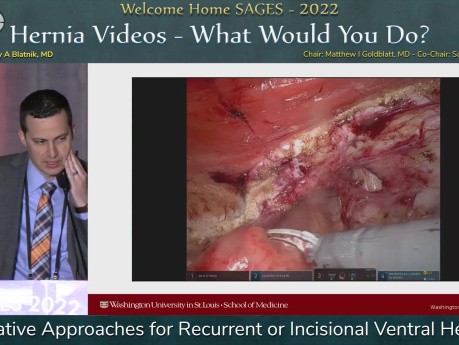

Abordajes quirúrgicos para hernias ventrales...

Esta charla se presentó en la sesión "Videos sobre hernias: ¿Qué harías tú?", a cargo de Jeffrey Blatnik, el 19 de marzo de 2022, durante la Reunión Anual de SAGES 2022 en Denver, Colorado.